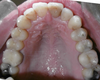

Avant